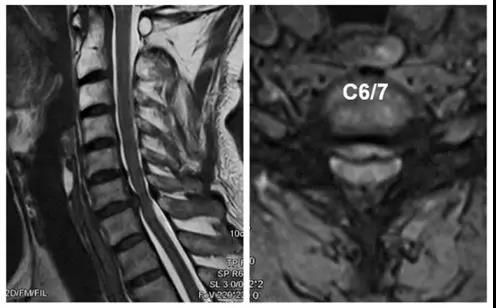

术前X线

术前CT

术前核磁

患者:男,51岁

主诉:双上肢麻木、疼痛一月,加重伴行走不稳3天

诊断:

1.颈椎间盘突出症(C6/7);

2.混合型颈椎病。